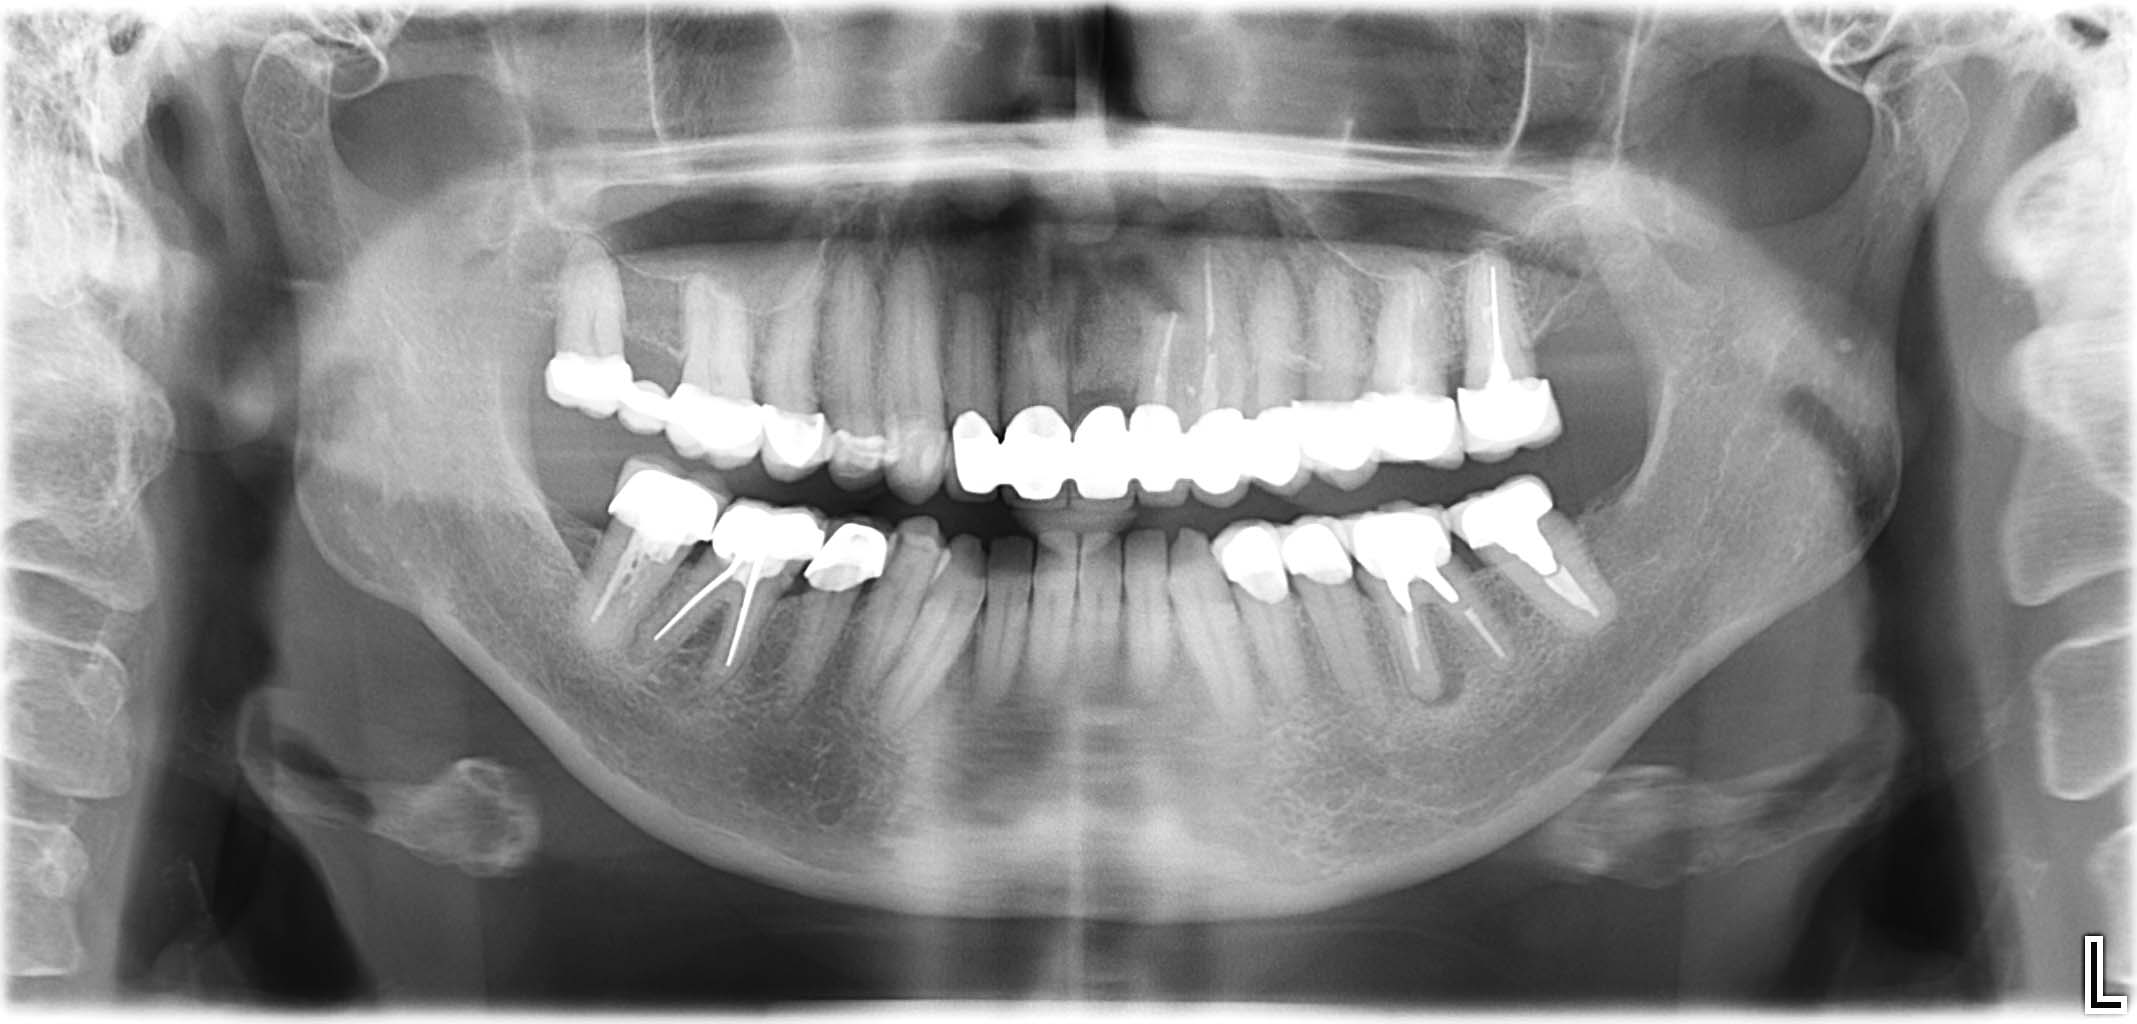

Erfolgreich implantierte Patientenfälle (klinische Fotos)